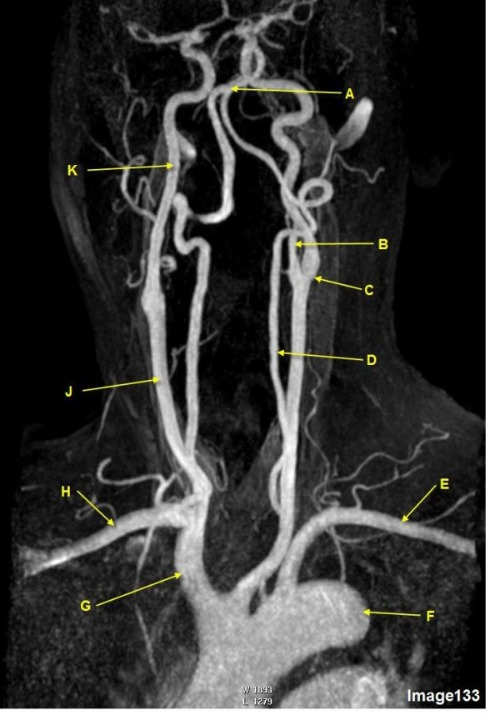

Image 16 is an example of what type of MR image?

E. MRA intracranial circulation

D. MRA extracranial circulation

Letter A in Image 16 is pointing to:

E. Common carotid bifurcation

B. External carotid artery

Letter B in Image 16 is pointing to:

A. Internal carotid artery

Letter C in Image 16 is pointing to:

D. Common carotid artery

Letter E in Image 16 is pointing to:

C. Vertebral artery

Letter C in Image 133 is pointing to:

E. External carotid artery

B. Common carotid bifurcation

Letter F in Image 133 is pointing to:

E. Subclavian artery

D. Thoracic aorta

Letter K in Image 133 is pointing to:

D. Internal carotid artery

Letter E in Image 133 is pointing to:

E. Aortic arch

B. Left subclavian artery

Letter D in Image 133 is pointing to:

A. Vertebral artery

Letter E in Image 16 is responsible for blood supply to the:

B. Posterior brain

Letter B in Image 16 is responsible for blood supply to the:

A. Anterior brain

Letter A in Image 16 is responsible for blood supply to the:

C. Face